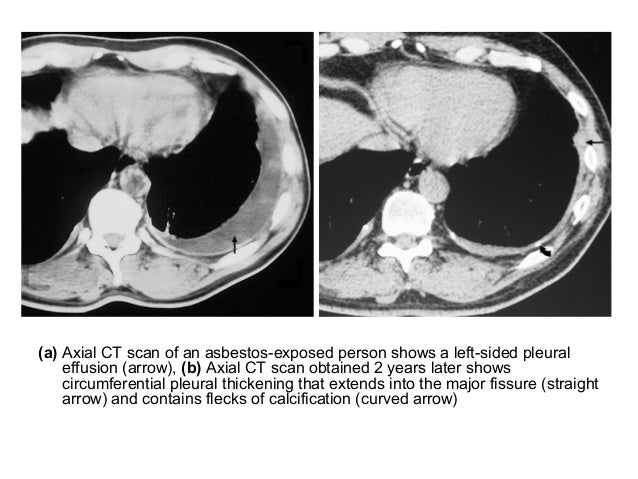

Asbestos Lung Ailment Ct